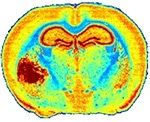

Left: A mouse brain tissue section analysis by IR microscopy showing the anatomical details of brain with tumor (left part) based on extracellular matrix distribution. FTIR acquisition lasted 12h for a 20-µm resolution while QCL-IR acquisition could be done in 1h50 with a 4.4-µm resolution.

The image shown is down-sampled by 8x8 due to file size limitations.

3D reconstruction of the tumor based on lipid/protein ratio. The tumor is presenting higher amount of proteins while brain is a “fatty” organ, thus making this ratio significantly different between tumor and healthy brain tissues.